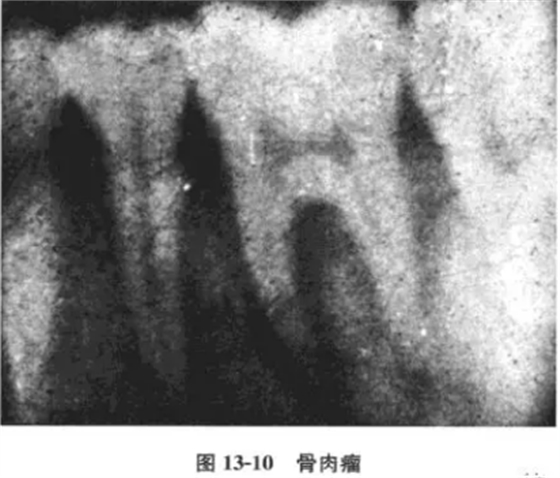

病例 男性,18歲,[6極度松動(dòng),咀嚼痛伴局部腫大而就診。檢查:[6III度松動(dòng),牙髓活力測(cè)試無(wú)反應(yīng),牙周袋3~5mm,左下頜角打及3mm×3mm之腫塊,邊界尚清,質(zhì)地中等偏軟,無(wú)壓痛,x線片示:[6兩根側(cè)及根分叉對(duì)稱(chēng)性牙周間隙增寬。為確診腫塊性質(zhì),轉(zhuǎn)口腔頜面外科,攝下頜骨正側(cè)位片,見(jiàn)左下頜角有溶骨性破壞,手術(shù)后病理診斷為骨肉瘤。

口腔頜面部肉瘤可分為軟組織肉瘤和骨源性肉瘤兩大類(lèi);骨肉瘤根據(jù)不同的病理表現(xiàn)又有骨纖維肉瘤、成骨性骨肉瘤、溶骨性骨肉瘤以及軟骨肉瘤等不同類(lèi)型。骨肉瘤起源于頜骨中心或牙槽內(nèi)者可早期表現(xiàn)為牙松動(dòng)、牙齦腫脹等類(lèi)似牙周炎的表現(xiàn)。x線攝片可見(jiàn)牙周間隙呈帶狀(或呈平行)增寬,而且常常是近遠(yuǎn)中同時(shí)發(fā)生。本病例因牙痛就診,牙髓活力無(wú)反應(yīng),伴牙松動(dòng)及牙周袋存在,若非在其后側(cè)觸及腫塊,極易誤診為牙周病及根尖周病,或牙髓牙周聯(lián)合病變。其x線片亦表現(xiàn)為較典型的早期骨肉瘤破壞陰影(圖13-10),為此,作為牙體牙髓科醫(yī)師必須具有此基本概念和知識(shí);更重要的是決不能忽視口腔頜面部的全面檢查,以保證診斷的正確性。